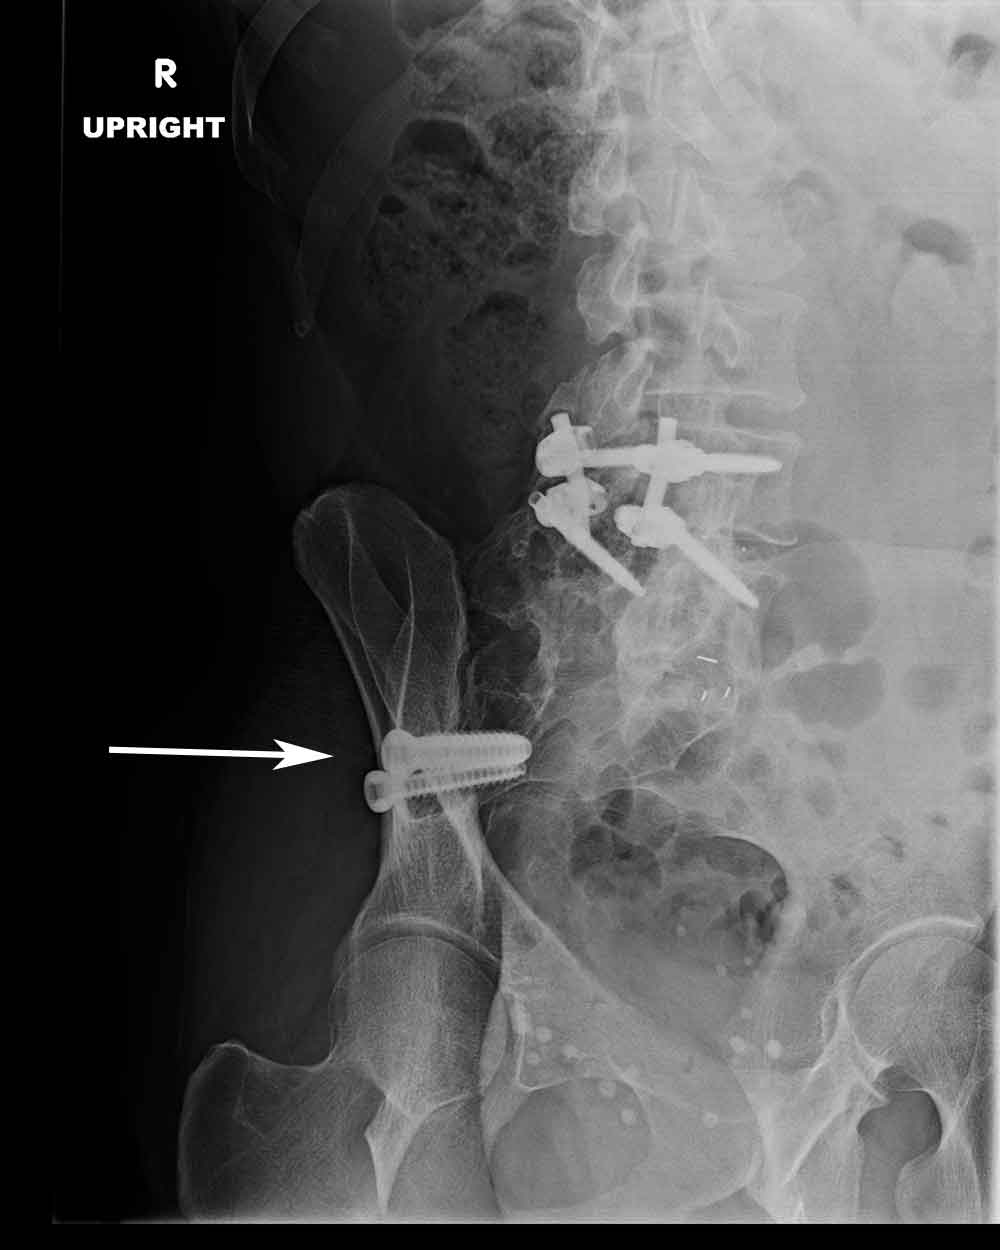

The Surgery Involves Placing Screws Or Other Hardware Across The Si Joint.

The threaded devices are offered in various lengths to accommodate your anatomy. The ifuse implant system, a minimally invasive surgical (mis) procedure, requires a small incision (about one to two inches long), along the side of the buttock. In a sacroiliac joint fusion, one or both sides of the sacrum is grafted to the ilium to encourage bone growth across the joint.

Si joint fusion recovery time is longer than a spinal fusion and can take up to 6 months to fully recover. Fusion of the si joint was seen in 68.7% of patients. The rialto si fusion system consists of cylindrical threaded devices designed to enhance sacroiliac joint fusion.